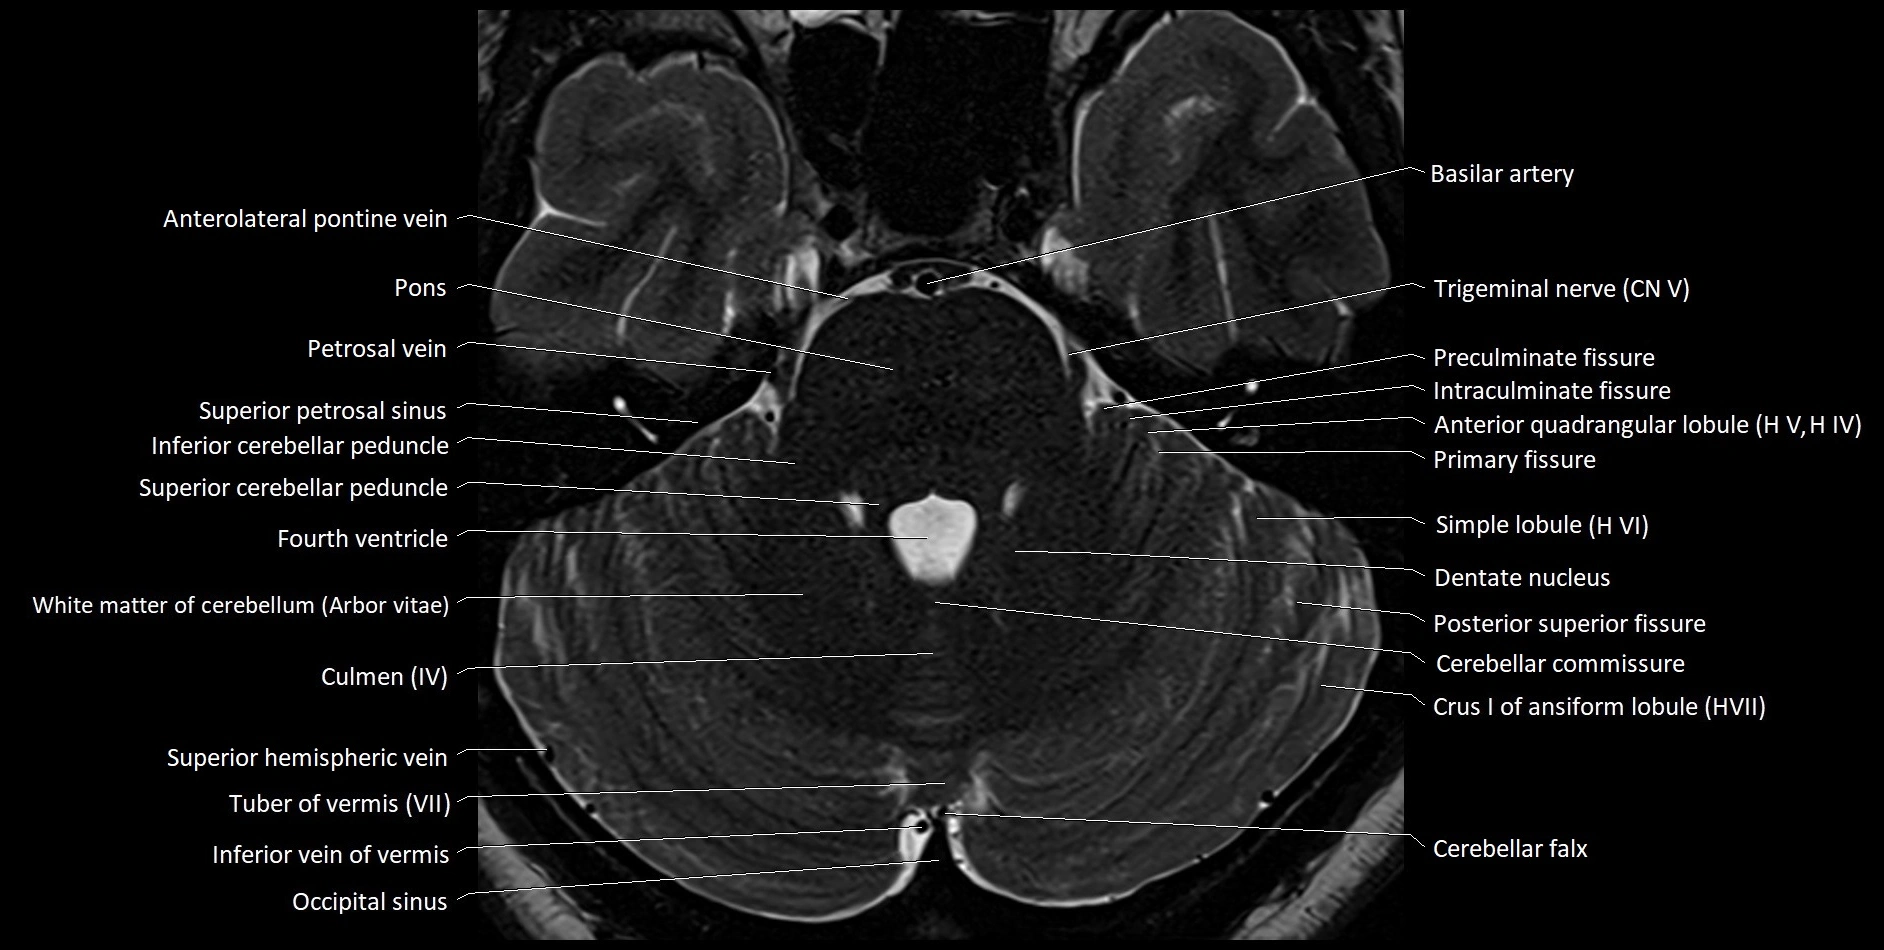

- Anterolateral pontine vein

- Middle cerebellar peduncle

- Inferior cerebellar peduncle

- Superior cerebellar peduncle

- Superior petrosal sinus

- Dentate nucleus

- Cerebellar commissure

- Crus I of ansiform lobule of cerebellum

- Simple lobule (HVI) of cerebellum

- Preculminate fissure

- Intraculminate fissure

- Primary fissure

- Culmen

- Culmen (IV, V) of Cerebellum

- Occipital sinus

- Tuber of vermis (VII)

- Inferior vein of vermis

- Cerebellar falx